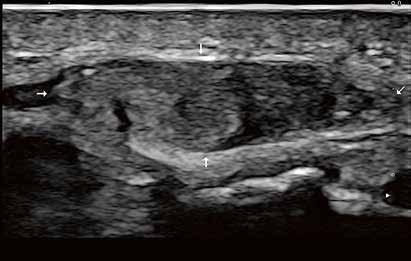

Hochauflösender Ultraschall in der Sportpraxis

Wie kamen Sie zur Sonographie?